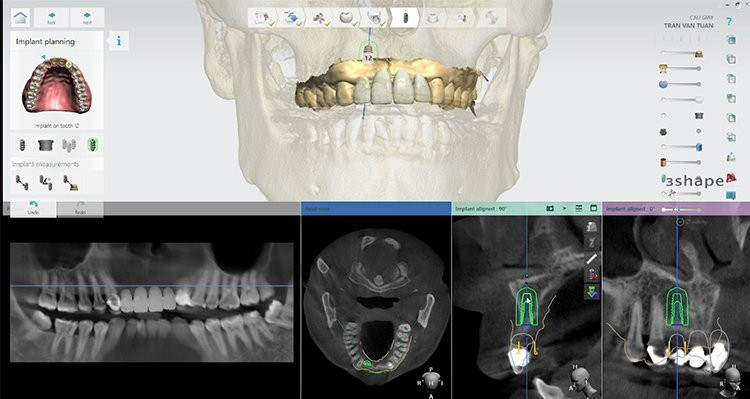

Virtual-X hỗ trợ bác sĩ lên kế hoạch điều trị chính xác nhất, giúp quá trình cấy ghép implant diễn ra an toàn nhất nhờ kết hợp 2 công nghệ là Smart-tech và 3D Guide.

![]() |

| Lên kế hoạch điều trị an toàn bằng công nghệ giả lập 3D |

“Để lập được một kế hoạch điều trị chính xác nhất, chúng tôi cần phải khảo sát tình trạng cũng như mật độ xương của khách hàng qua hình ảnh trên phim CT Cone Beam. Các dữ liệu về xương hàm, mô lợi, tình trạng răng và khớp cắn của bệnh nhân được tái lập lại trên phần mềm giả định và chúng tôi sẽ đặt trụ implant giả định vào vị trí chính xác trong xương hàm ngay trên phần mềm này. Sau đó, những dữ liệu này được chuyển qua phần mềm Exocad để thiết kế ra máng hướng dẫn phẫu thuật 3D Guide. Loại máng này được sản xuất bằng công nghệ CAD/CAM với vật liệu PMMA không bị biến dạng trong mọi môi trường.

Máng hướng dẫn phẫu thuật 3D Guide chính là trợ thủ đắc lực hỗ trợ bác sĩ đặt chân răng implant theo 3 chiều trong không gian. Phương pháp này đảm bảo tính chính xác gần như tuyệt đối với tỉ lệ sai số dưới 0,001%. Trụ implant được cấy ghép bằng máng 3D Guide sẽ đạt được khoảng phục hình tối ưu nhất, tăng tính thẩm mỹ tối đa cho phục hình răng sứ.”- Bác sĩ Nguyễn Hoàng Dương chia sẻ về ưu điểm của kỹ thuật Virtual-X trong công nghệ trồng răng implant DCT.